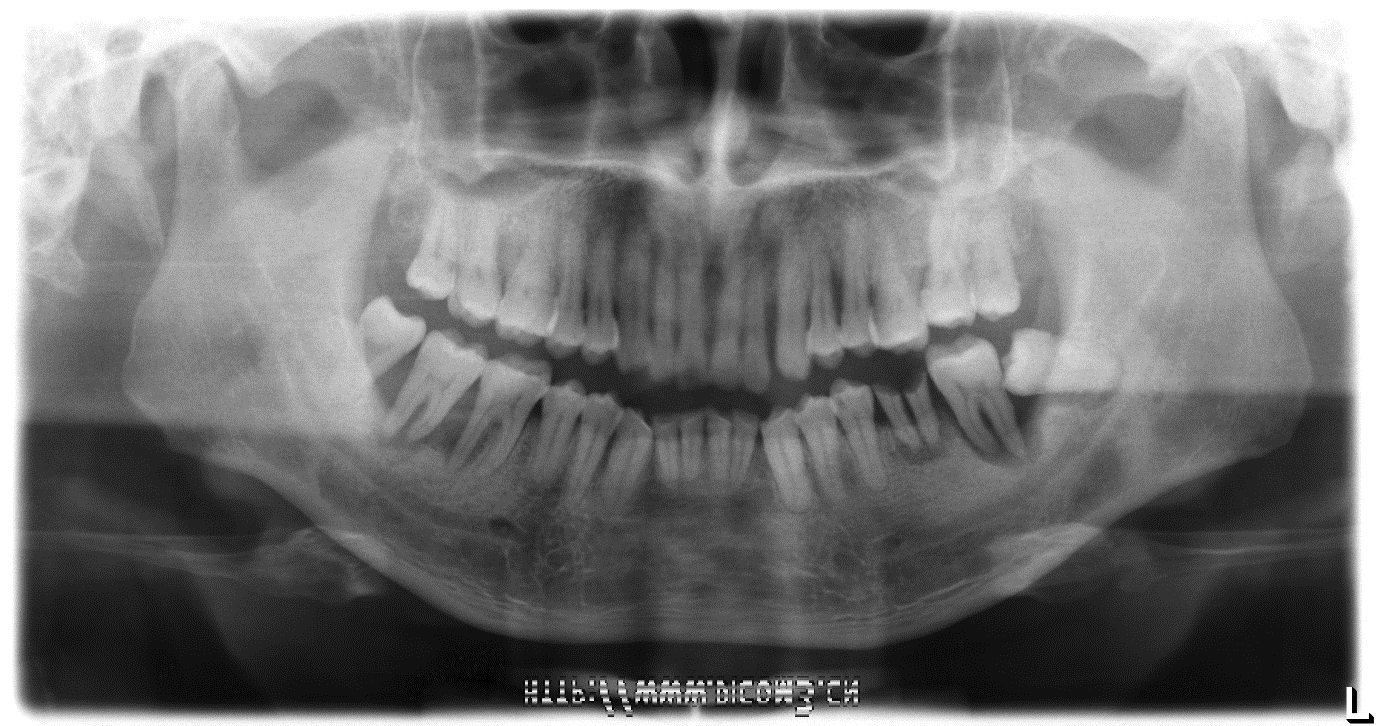

陈医生结合多年的临床经验,通过大量的临床病例图片,全方位向大家展示了牙周病的病因、治疗过程及修复手段,普及了丹麦Genius水冷激光的适应症,详细介绍了丹麦Genius水冷激光的优势,如何用水冷激光治疗牙周病以及牙齿的清洁与牙周病的预防方法和手段。

陈家芳医师客户案例分析